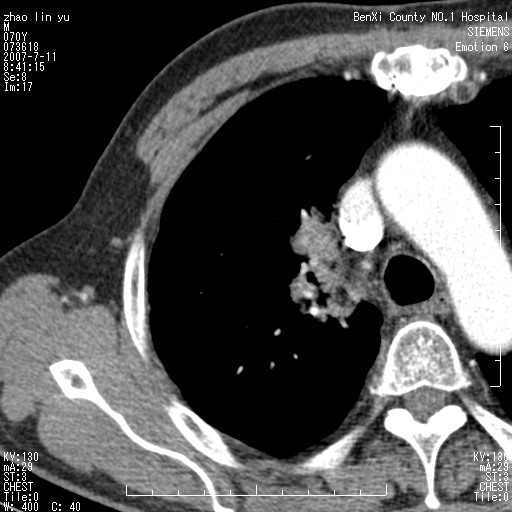

以下是引用王靖旗在2007-7-10 17:12:00的发言:[br] 男、70、咳嗽两个月,半年前换瓣手术,胸片未见异常,于昨天行x片发现右肺上野大片影,行ct扫描,这里是减薄图像,余肺正常。明天晚上会有增强扫描片,到时我会上传。[br][br] 冠状位请大家细看,应该是有意义的,[br][br] 请大家先看平扫发表意见。[br][br]

以下是引用zhangzhongshou在2007-7-10 21:43:00的发言:[br]右肺上叶周围型肺癌,以孤立型细支气管肺泡癌可能性大。